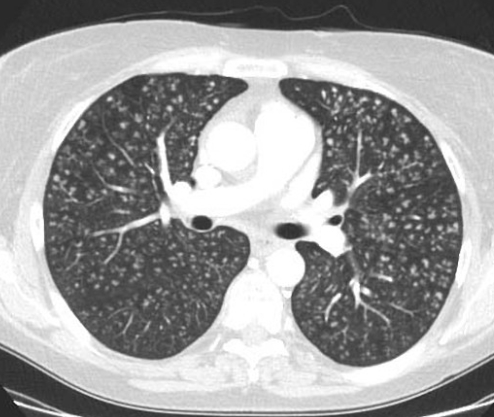

Очаг – локальное уплотнение легочной ткани размером до 1см, окруженное со всех сторон легочной тканью и/или висцеральной плеврой. Термин «очаг» применяется к одиночным или единичным (числом не более 6 в каждом легком) уплотнениям легочной ткани. Множественные очаги, имеющие, как и одиночные, размеры менее 10мм, обычно определяются как легочные (очаговые) диссеминации.

Очаговые изменения в легких, или очаги – термин, который используется в медицине для описания ограниченных участков патологических изменений в легочной ткани, причем очень маленьких, в отличие, например, от пневмонии. В России очагом принято считать локальное уплотнение легочной ткани диаметром до 10мм.

Они могут быть обнаружены при рентгенографии или, чаще, компьютерной томографии, так как она имеет отличное пространственное разрешение, то есть организм, или в нашем случае легкие, можно как бы порезать тоненькими слоями поперек по 1мм. С такой разрешающей способностью неудивительно, что у довольно большого процента людей обнаруживается хотя бы один очаг.

- солидные – ударение на первый слог, они так называются не потому, что какие-то крупные или вызывающие восхищение по другому поводу, а потому, что в переводе означает «твердые, плотные», то есть сквозь них не видно остальную ткань легкого;